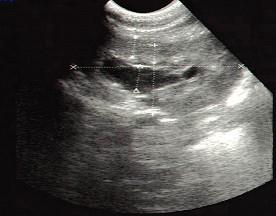

问题 诊断肾积水首先应做的检查是 ( )

选项 A、逆行造影 B、B超 C、IVU D、KUB+IVP E、KUB

答案 B